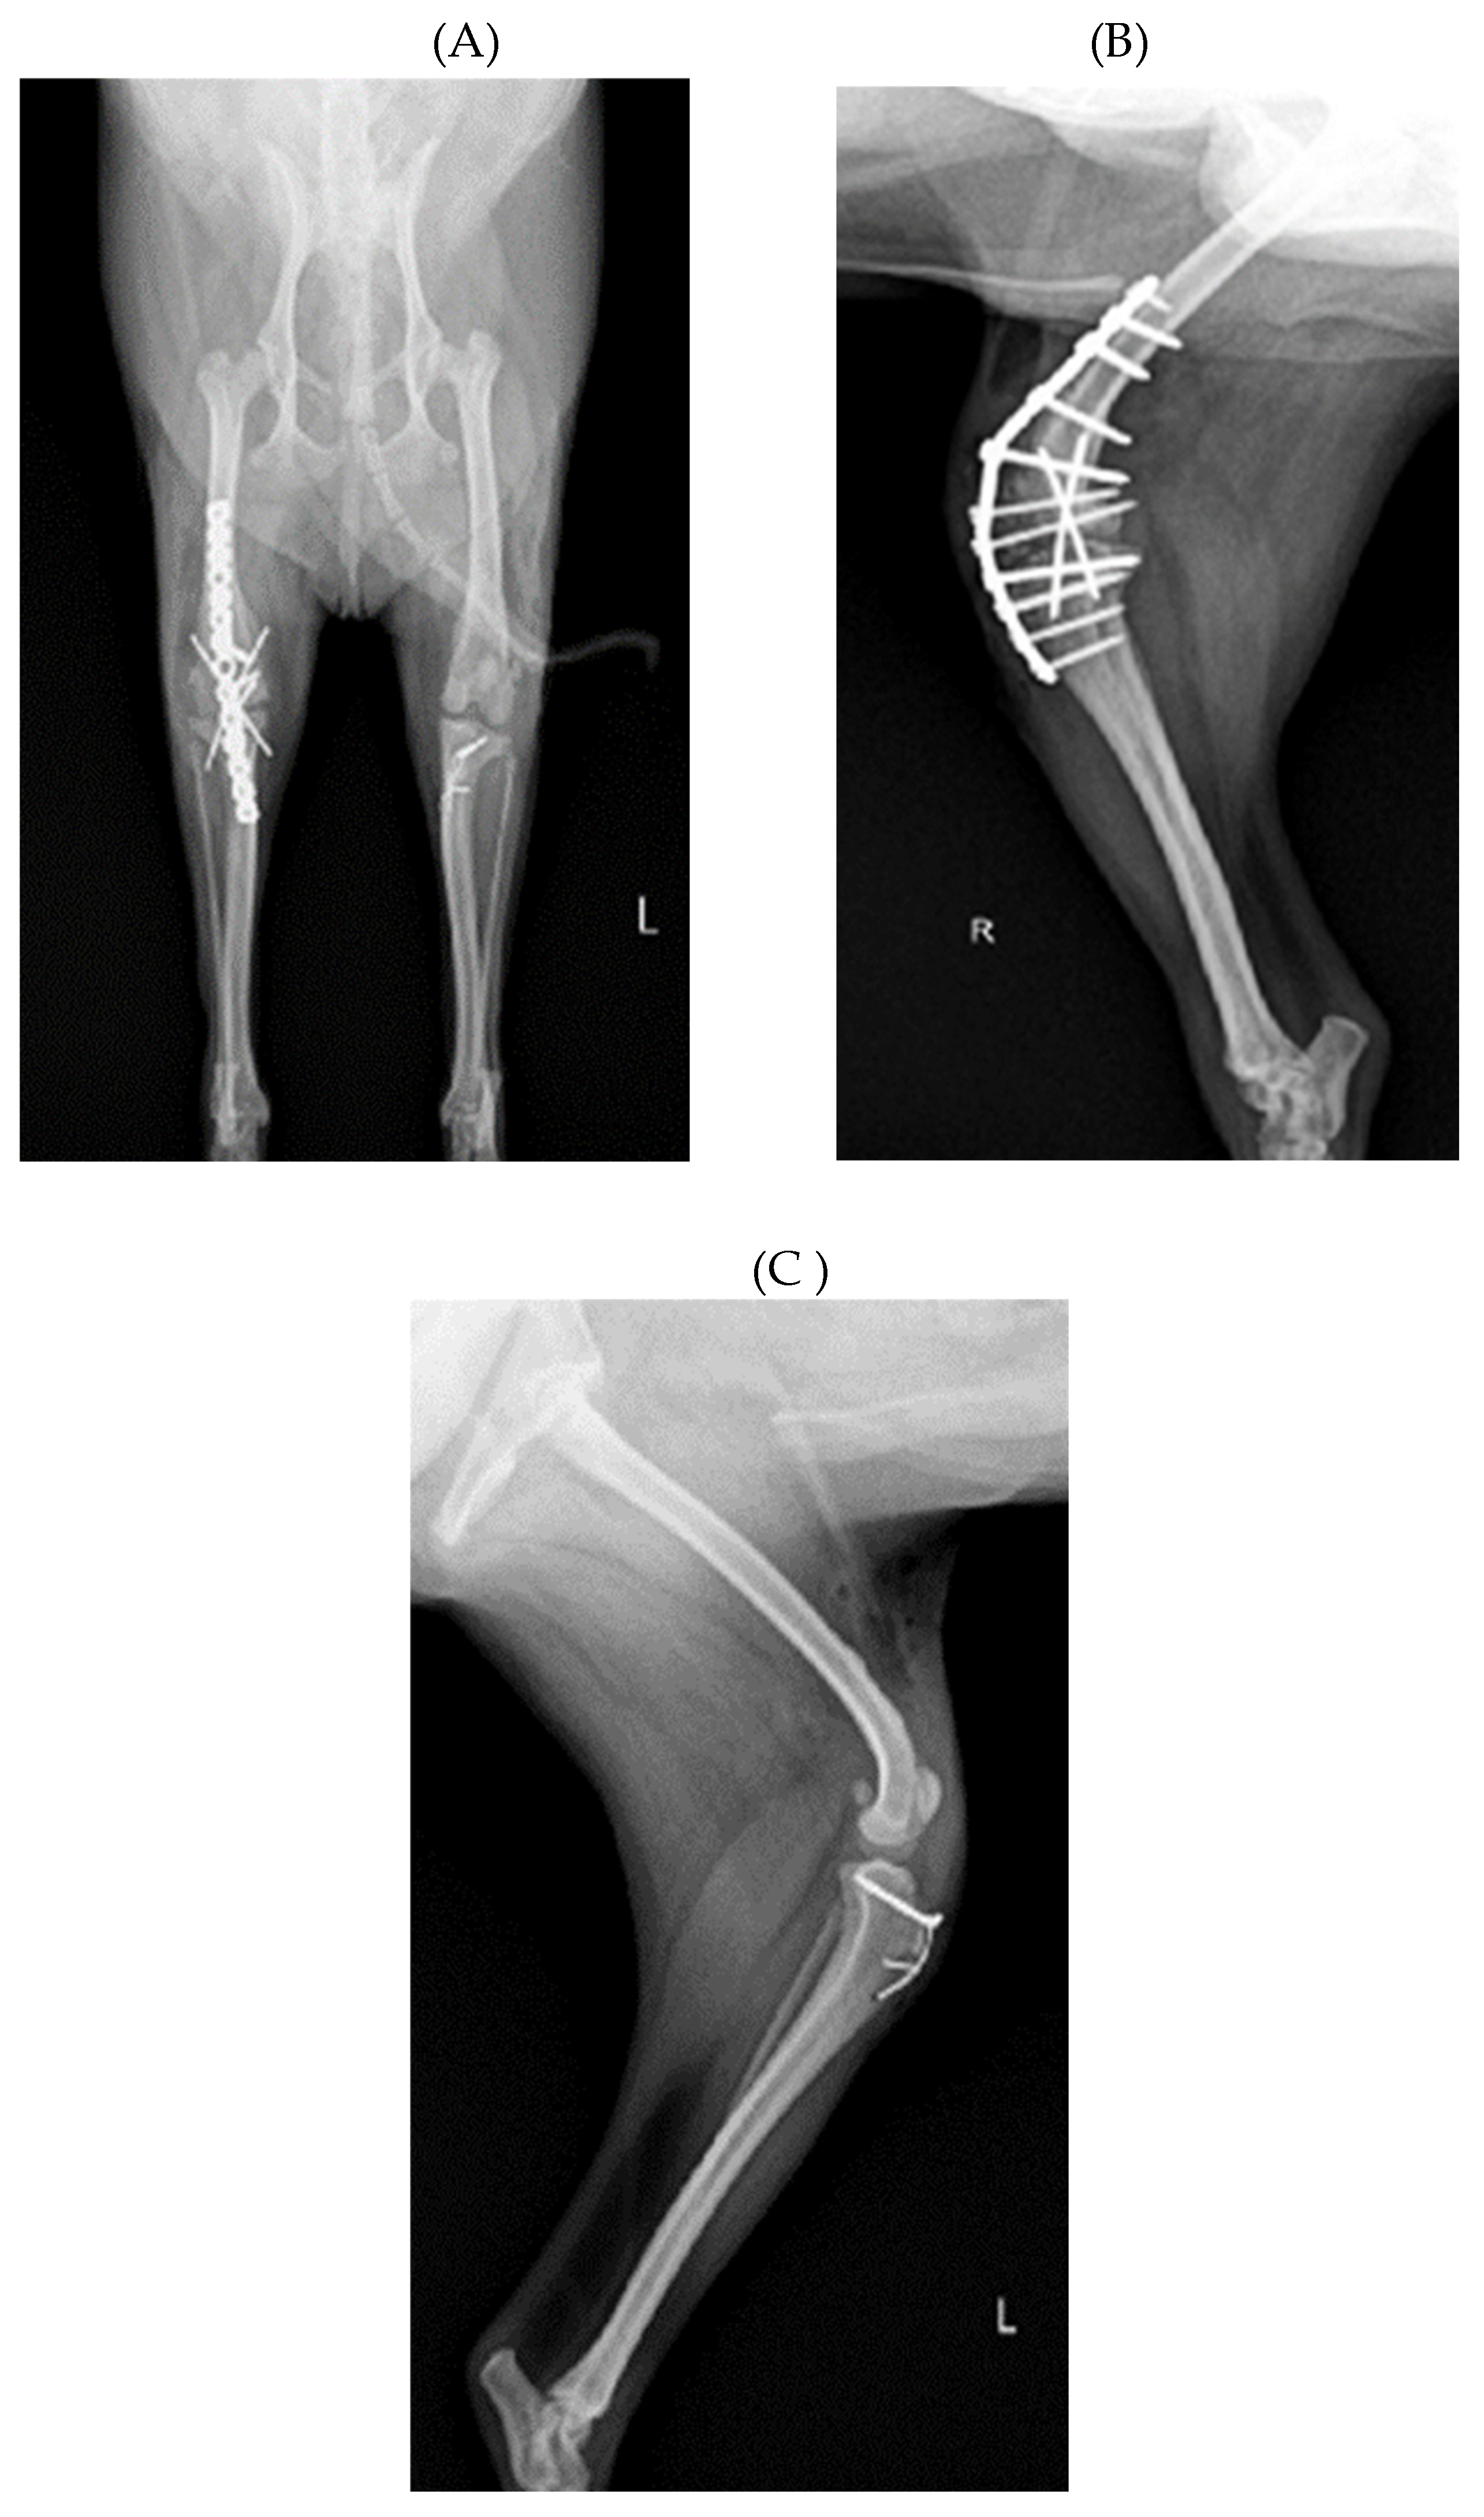

Before surgery, antibiotic and anti-inflammatory drugs were applied for about a month to relieve pain, edema and arthritis, and then the surgery was performed. For treatment, amoxicillin/clavulanic acid (Amocla, KUHNIL corp., 12.5 mg/kg) and carprofen (RIMADYL, Zoetis Inc., 2.2 mg/kg) were prescribed bid for 4 weeks. After one month, radiographic findings confirmed that inflammation and edema in both stifle joints were reduced (Figure 2). The owner was informed that stifle joint arthrodesis was to be performed on the right hind limb due to severe osteoarthritis, loss of the patella and rupturing of the cranial cruciate ligament, and that MPL correction was to be performed on the left leg, and the consent of the guardian was obtained.

Figure 2. Preoperative craniocaudal (A) and mediolateral (B, C) radiograph of the right and left stifle joints. Antiinflammatory drugs reduced pain, lower fever, and decrease in-flammation (swelling and damage) after the drugs applied for about a month. Arrow showed images with significantly reduced inflammation and edema compared to a month ago.

Figure 4. Radiograph images performed the stifle joint arthrodesis on right hind limbs and the medial patellar luxation correction on the left hind leg. (A) Craniocaudal radiographic view of the both stifle joint. (B) Medioalteral radiopraphic view of stifle joints following SJA. (C) Postoperative mediolateral view of MPL in the left hindlimb.